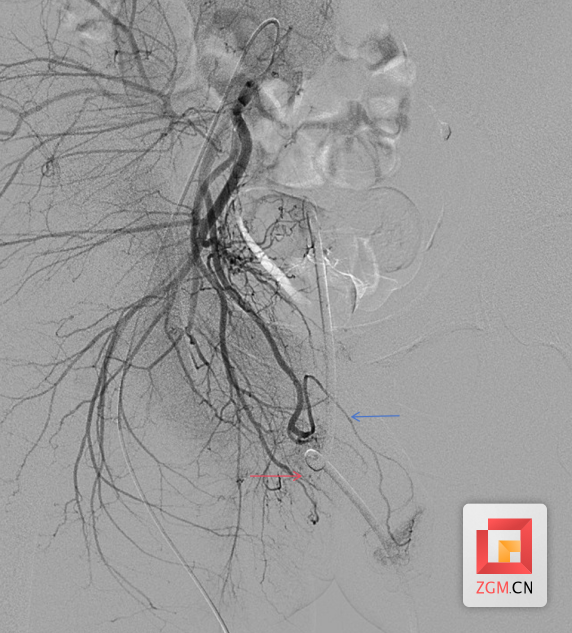

术中,介入手术中心医生在DSA(数字减影血管造影)引导下,将一根细如发丝的微导管,精准探入患者盆腔内的“犯罪血管”——阴部内动脉分支。随着造影剂的注入,屏幕上清晰地显示出了异常出血点。随即,医务人员通过微导管注入微小的栓塞材料,成功将出血点精准封堵。再次造影显示:出血信号消失,血流通畅,周围正常血管网毫发无损。